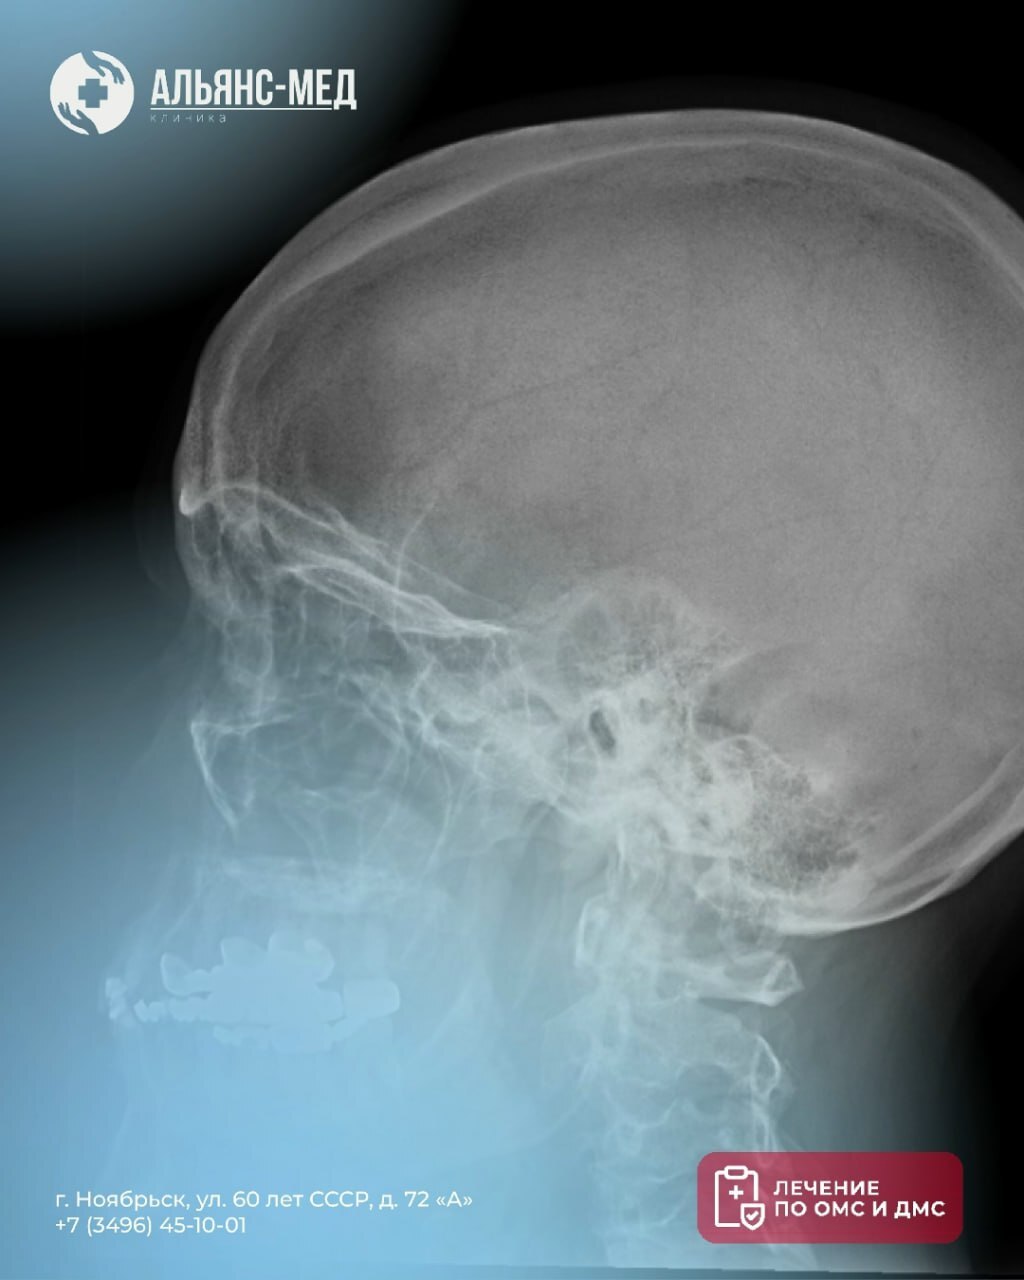

Что покажет снимок?

· Переломы костей черепа

· Трещины и смещения

· Гематомы

· Признаки повышенного внутричерепного давления

· Состояние пазух носа и височно-нижнечелюстных суставов